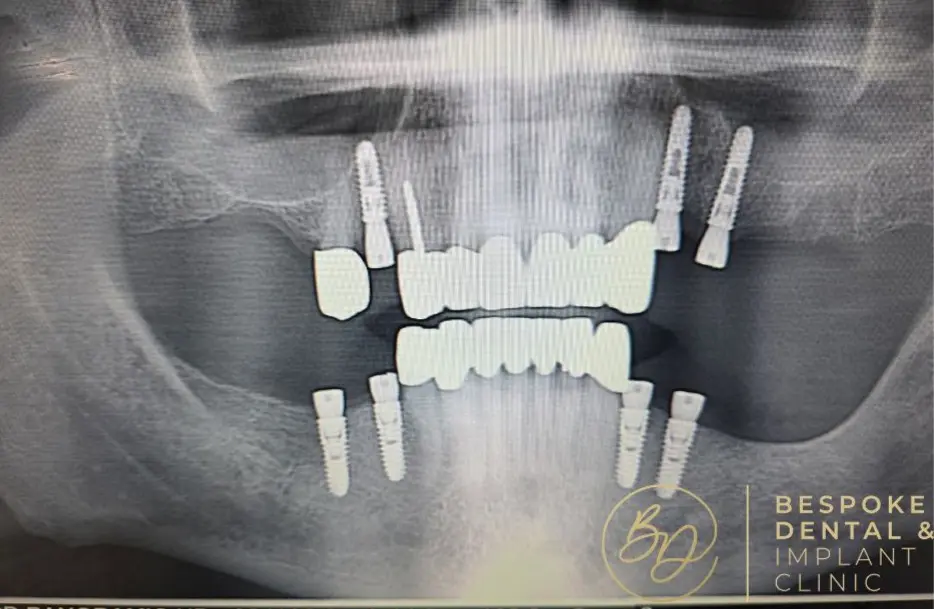

Full mouth

dental implants

Single Jaw

from £12,000

Full Mouth Implants

from £22,000

All Inclusive:

Surgery

Implants

IV Sedation

Zirconia Implant Bridges

5 Years Warranty